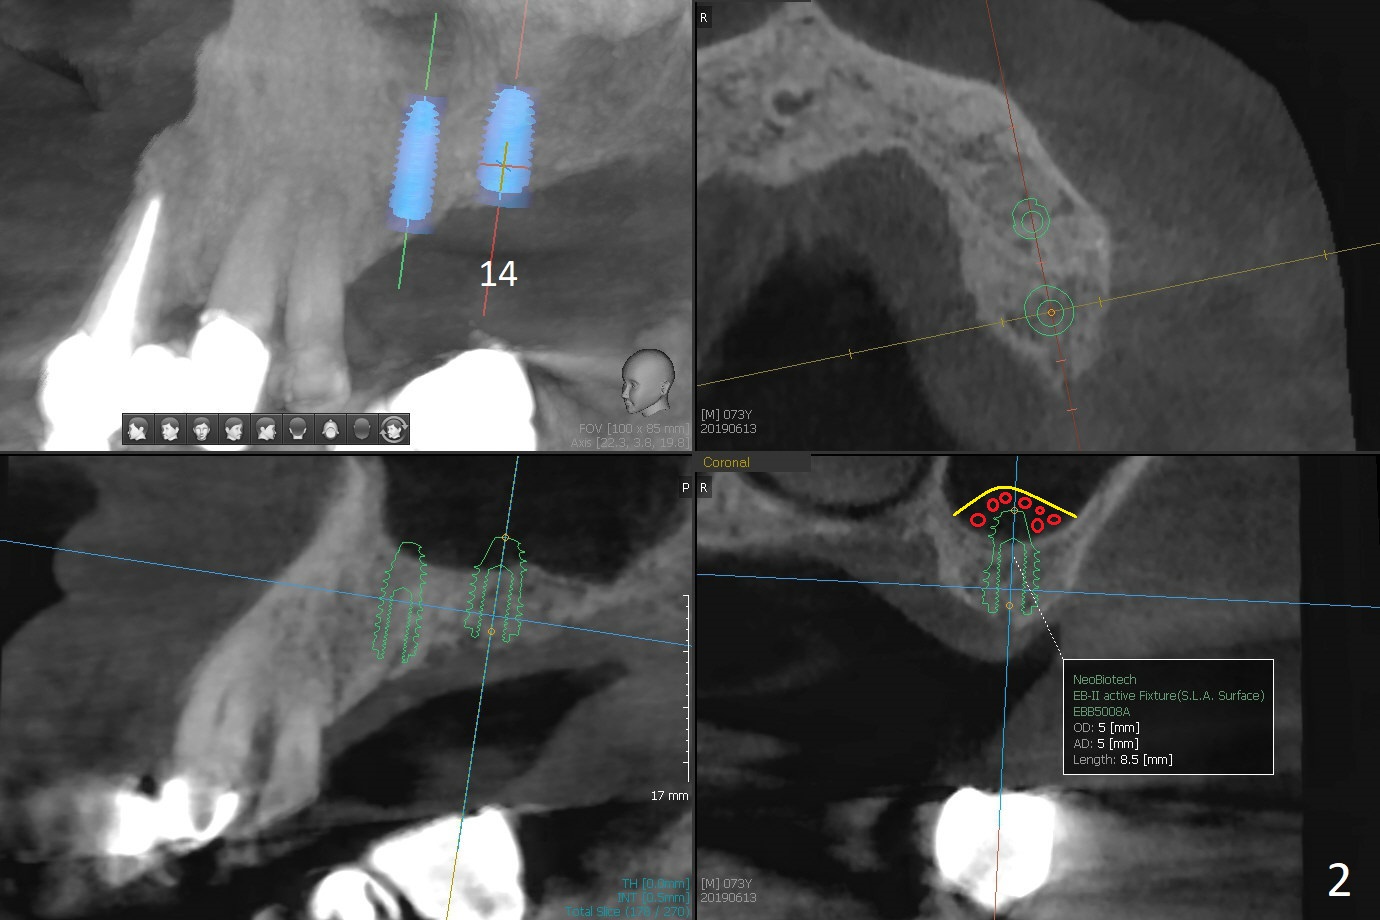

A 73-year-old man returns for #13 and 14 implants (guide) following #19 and 29-31 ones (Fig.1,2). Sinus lift (Fig.2 red circle) will be also assisted with guide and PRF at #14 (yellow curved line (Metronidazole)).